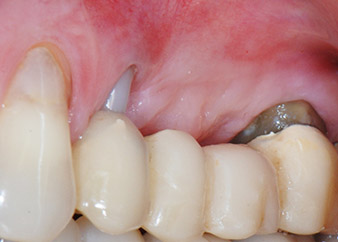

kompletter Verlust von Knochen und Attachment

Abb. 2 und 3: Bei der Freilegung einen Monat nach endodontischer Revision und Beginn einer systematischen Parodontalbehandlung weist die bukkale Wurzel des Zahns 24 einen kompletten Verlust von Knochen und Attachment auf.

Einen Monat nach dem Eingriff waren sowohl die Schmerzen als auch die Entzündung an Zahn 24 minimal, die Zahnbeweglichkeit lag jedoch noch bei Miller-Klasse 2. Nach Freilegung und Reinigen des infizierten periapikalen und periradikulären Gewebes wurde das Ausmaß des Knochendefizits deutlich (Abb. 2 und 3).

An der bukkalen Wurzel fehlte der gesamte vestibuläre und distale Knochen. Das Attachment beschränkte sich weitgehend auf die palatinale Wurzel, was die anfängliche schlechte Prognose unterstreicht. Auch Zahn 27 wies ein verringertes horizontales Attachment (vgl. Abb. 12) und eine kleine apikale Aufhellung (Abb. 1) auf, allerdings ohne klinische Symptome.